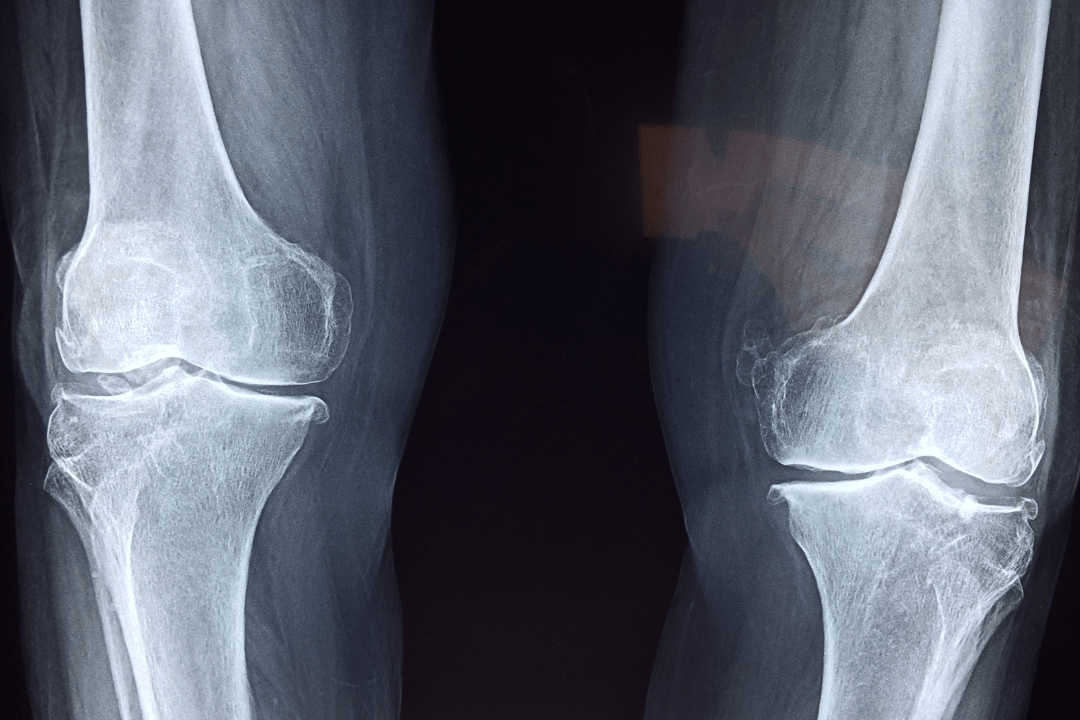

単なる見た目の問題として捉えられがちですが、O脚に「痛み」や「こわばり」「違和感」が伴う場合、膝関節の中でクッションの役割を果たす軟骨がすり減る「変形性膝関節症(へんけいせいひざかんせつしょう)」という病気が発症・進行している可能性が高いと考えられます。

O脚の状態は、膝の内側に体重の負担が極端に集中しやすい構造になっています。そのため、長年の負荷が蓄積することで内側の軟骨がすり減りやすく、進行すると骨同士が直接ぶつかって強い炎症や痛みを引き起こしてしまうのです。

正常なまっすぐの脚であれば、歩くときや立つときの体重の負担は、膝関節全体に均等に分散されます。しかし、O脚になって膝が外側に湾曲(わんきょく)すると、力学的なバランスが崩れ、体重の負担が「膝関節の内側」に極端に偏ってしまいます。

長年この状態が続くと、特定の局所(内側)ばかりに強い摩擦と圧力がかかり続け、クッションである軟骨が少しずつ摩耗し、すり減っていくのです。

一度すり減ってしまった軟骨は、髪の毛や皮膚のように自然に再生することは原則としてありません。これが「変形性膝関節症」の発症と進行のメカニズムです。